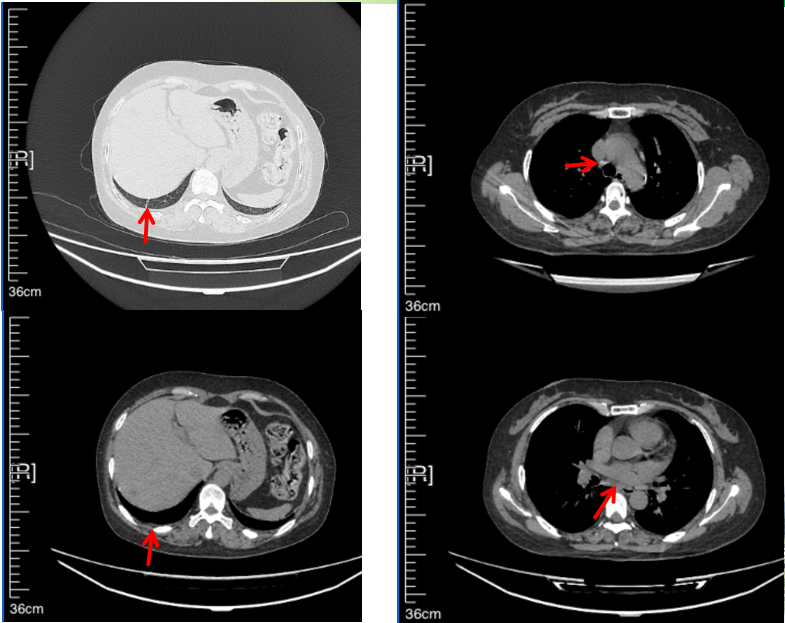

2016年1月复查CT提示支气管截断可见新发小结节,一线治疗采用培美曲塞+DDP方案化疗4周期(培美曲塞3.36,DDP 480mg)。化疗后复查胸部CT:右肺见不规则结节样影,最大层面大小约19mm*8mm,较前比较明显增大,疗效评估PD。2017.3-2017.4予单药多西他赛化疗3周期,疗效评估SD。2018年5月末复查CT提示结节较前增大,评效为PD,2018年6-10月予多西他赛+CBP化疗4周期,疗效评估SD。2022年5月患者出现活动后气短,复查胸部CT示右肺膨胀不良;右侧胸腔积液增多。胸腔积液包埋病理示符合肺腺癌细胞。行NGS基因检测:EML4:exon13-ALK:exon20融合。PD-L1(克隆号22C3)TPS<1%。

临床诊断:右肺上叶恶性肿瘤rT0N0M1a IVA期(第9版分期);恶性胸腔积液。

诊疗经过:2022年5月始口服克唑替尼3个月,出现肝功能异常(DILI 2级伴临床症状),改用恩沙替尼靶向治疗至今,目前评效为维持PR。恩沙替尼应用期间出现轻度肝功能异常(DILI 1级),对症处理后好转。截止目前PFS 33个月。

2018.07

2022.05

2022.08

2023.05

2024.12